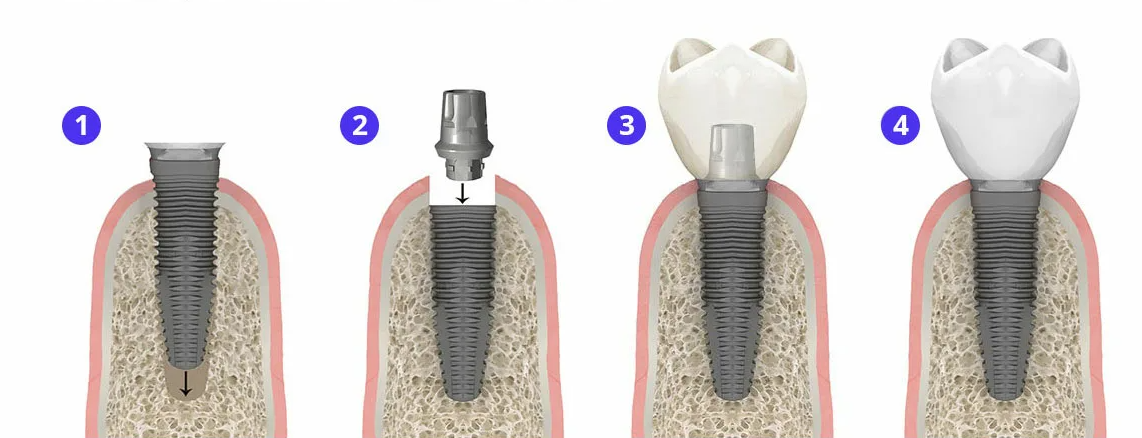

Имплантация зубов: этапы проведения

Современные импланты состоят из нескольких частей:

- Штифта (имплант);

- абатмента;

- коронки.

Штифт изготавливается из титана и выполняет роль нового корня зуба. Медицинский титан, который применяется для его изготовления, не отторгается. На корне присутствует резьба для установки в челюсть. Успешная имплантация зубов гарантирована в 99% случаев. При процедуре остеоинтеграции учитывают такие факторы, как возраст пациента, состояние здоровья, объем костной ткани в месте установки, количество зубов, которые нужно возместить. Учитывается и общее количество отсутствующих зубов в челюсти.

Имплантация зубов проходит в несколько этапов. Сначала с пациентом проводится консультация, по итогам которой подбирают тип имплантов. На второй стадии устанавливается искусственный корень - штифт, а также абатмент. Рану ушивают, дожидаются ее заживления. Если не произошло отторжение импланта, приступают к третьей стадии - установке коронки. Ее изготавливают в зубопротезной лаборатории.